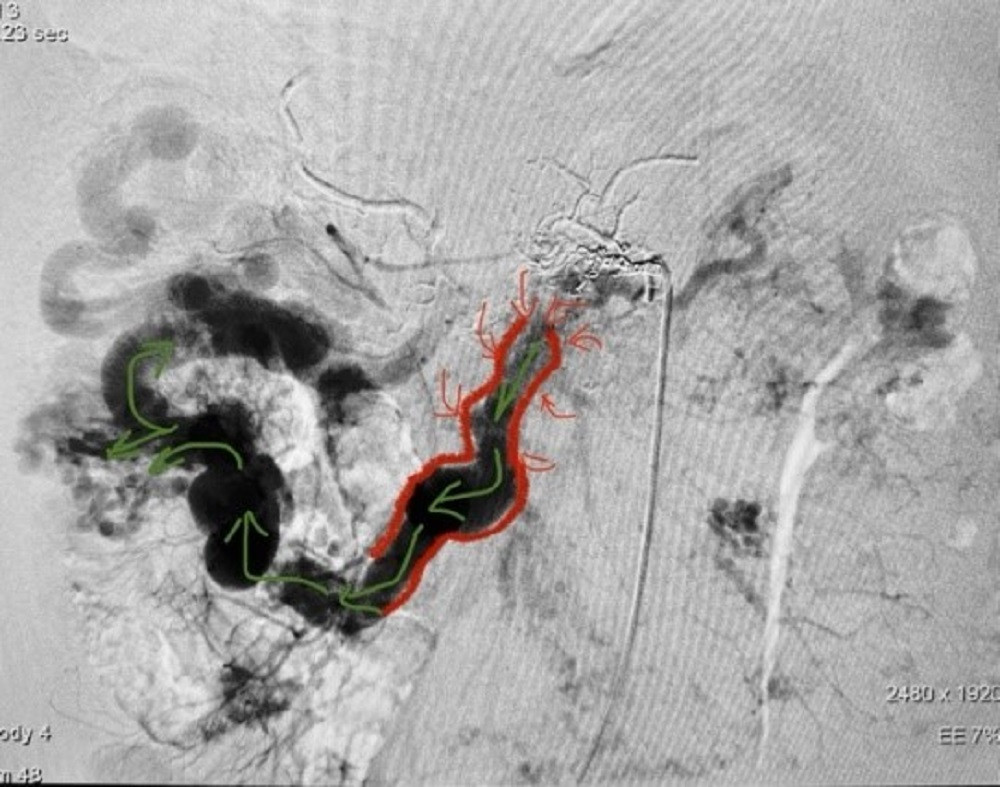

| Hình ảnh kiểm tra ghi nhận tình trạng bệnh rất phức tạp bệnh nhân phải đối mặt |

Kết quả chụp cắt lớp vi tính (CT-scan) vùng bụng phát hiện tắc mạn tính tĩnh mạch cửa, chuyển dạng xoang hang (tái cấu trúc giãn lớn hệ thống mạch máu do tắc mạn tính) ở vùng rốn gan, nguyên nhân chính gây chảy máu là dị dạng và thông nối động - tĩnh mạch ruột lan toả gây giãn các nhánh tĩnh mạch mạc treo ruột. Bên cạnh đó, bệnh nhân còn bị huyết khối tĩnh mạch cửa mạn tính.